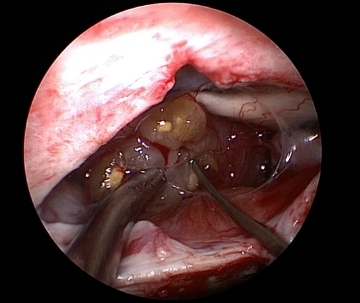

4)脳実質内腫瘍

頭蓋骨に12mm程度の穴を作成し、9mm細いポートと内視鏡、そして専用の道具を用いて、脳の損傷を最小限に抑え、腫瘍を摘出します。脳内の白質線維を描出し、重要な連絡路を保存しながら手術を行います。